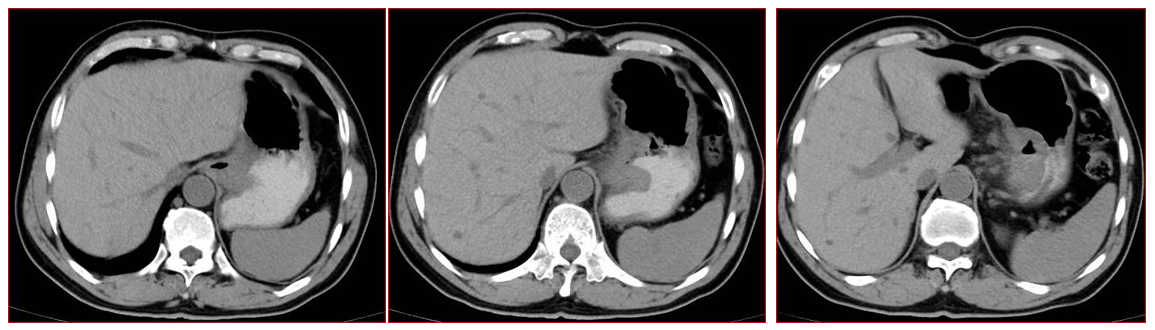

腹部CT:胃体上部小弯侧可见不规则增厚,回声减低、上下范围约7.4cm,可探及范围2.9*1.6cm凹陷面,表面可见斑点状强回声附着,局部浆膜层回声中断。胃周可见多个肿大淋巴结,较大者约0.7cm(图1)。

17.3.png图1. 腹部CT检查(基线)